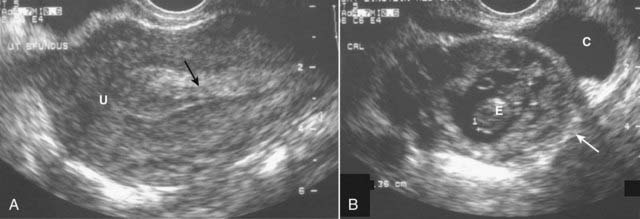

image

Figure 19-14 Normal uterus, sagittal (A) and transverse (B).

The uterus (solid white arrows) has a pear shape with maximum dimensions of approximately 8 cm in length, 5 cm in width, and 4 cm in AP dimension. A, The endometrium lines the uterine cavity and is measured in the sagittal view (solid black arrows). B, The collapsed uterine cavity is within the center of the endometrium and is visualized as a thin, echogenic line (dotted white arrow).